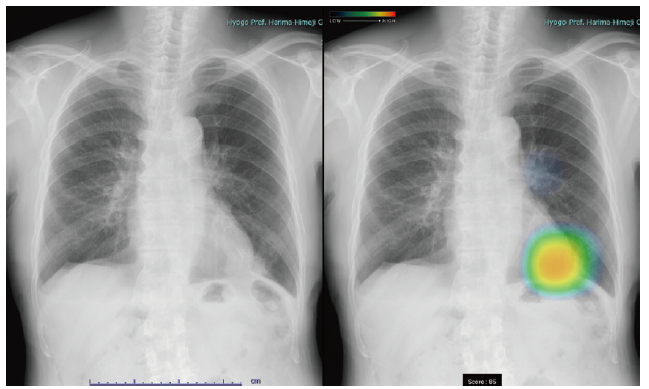

近年、胸部画像の見落としによる診断遅れが医療過誤として報道されるケースが散見されます。こうした背景を受け、当院では2024年5月より、胸部X線画像を自動解析・判読するソフトウェアを導入しました。

医師の見落としを防ぐ助けとなるだけでなく、画面上で異常部位を分かりやすく示してくれるため、患者さんにもご自身の病状を理解していただきやすくなったと実感しています。胸部に異常陰影が見られる患者さんがいらっしゃいましたら、分かりやすく病状を提示することができますので、ぜひ当院へのご紹介をご検討ください。